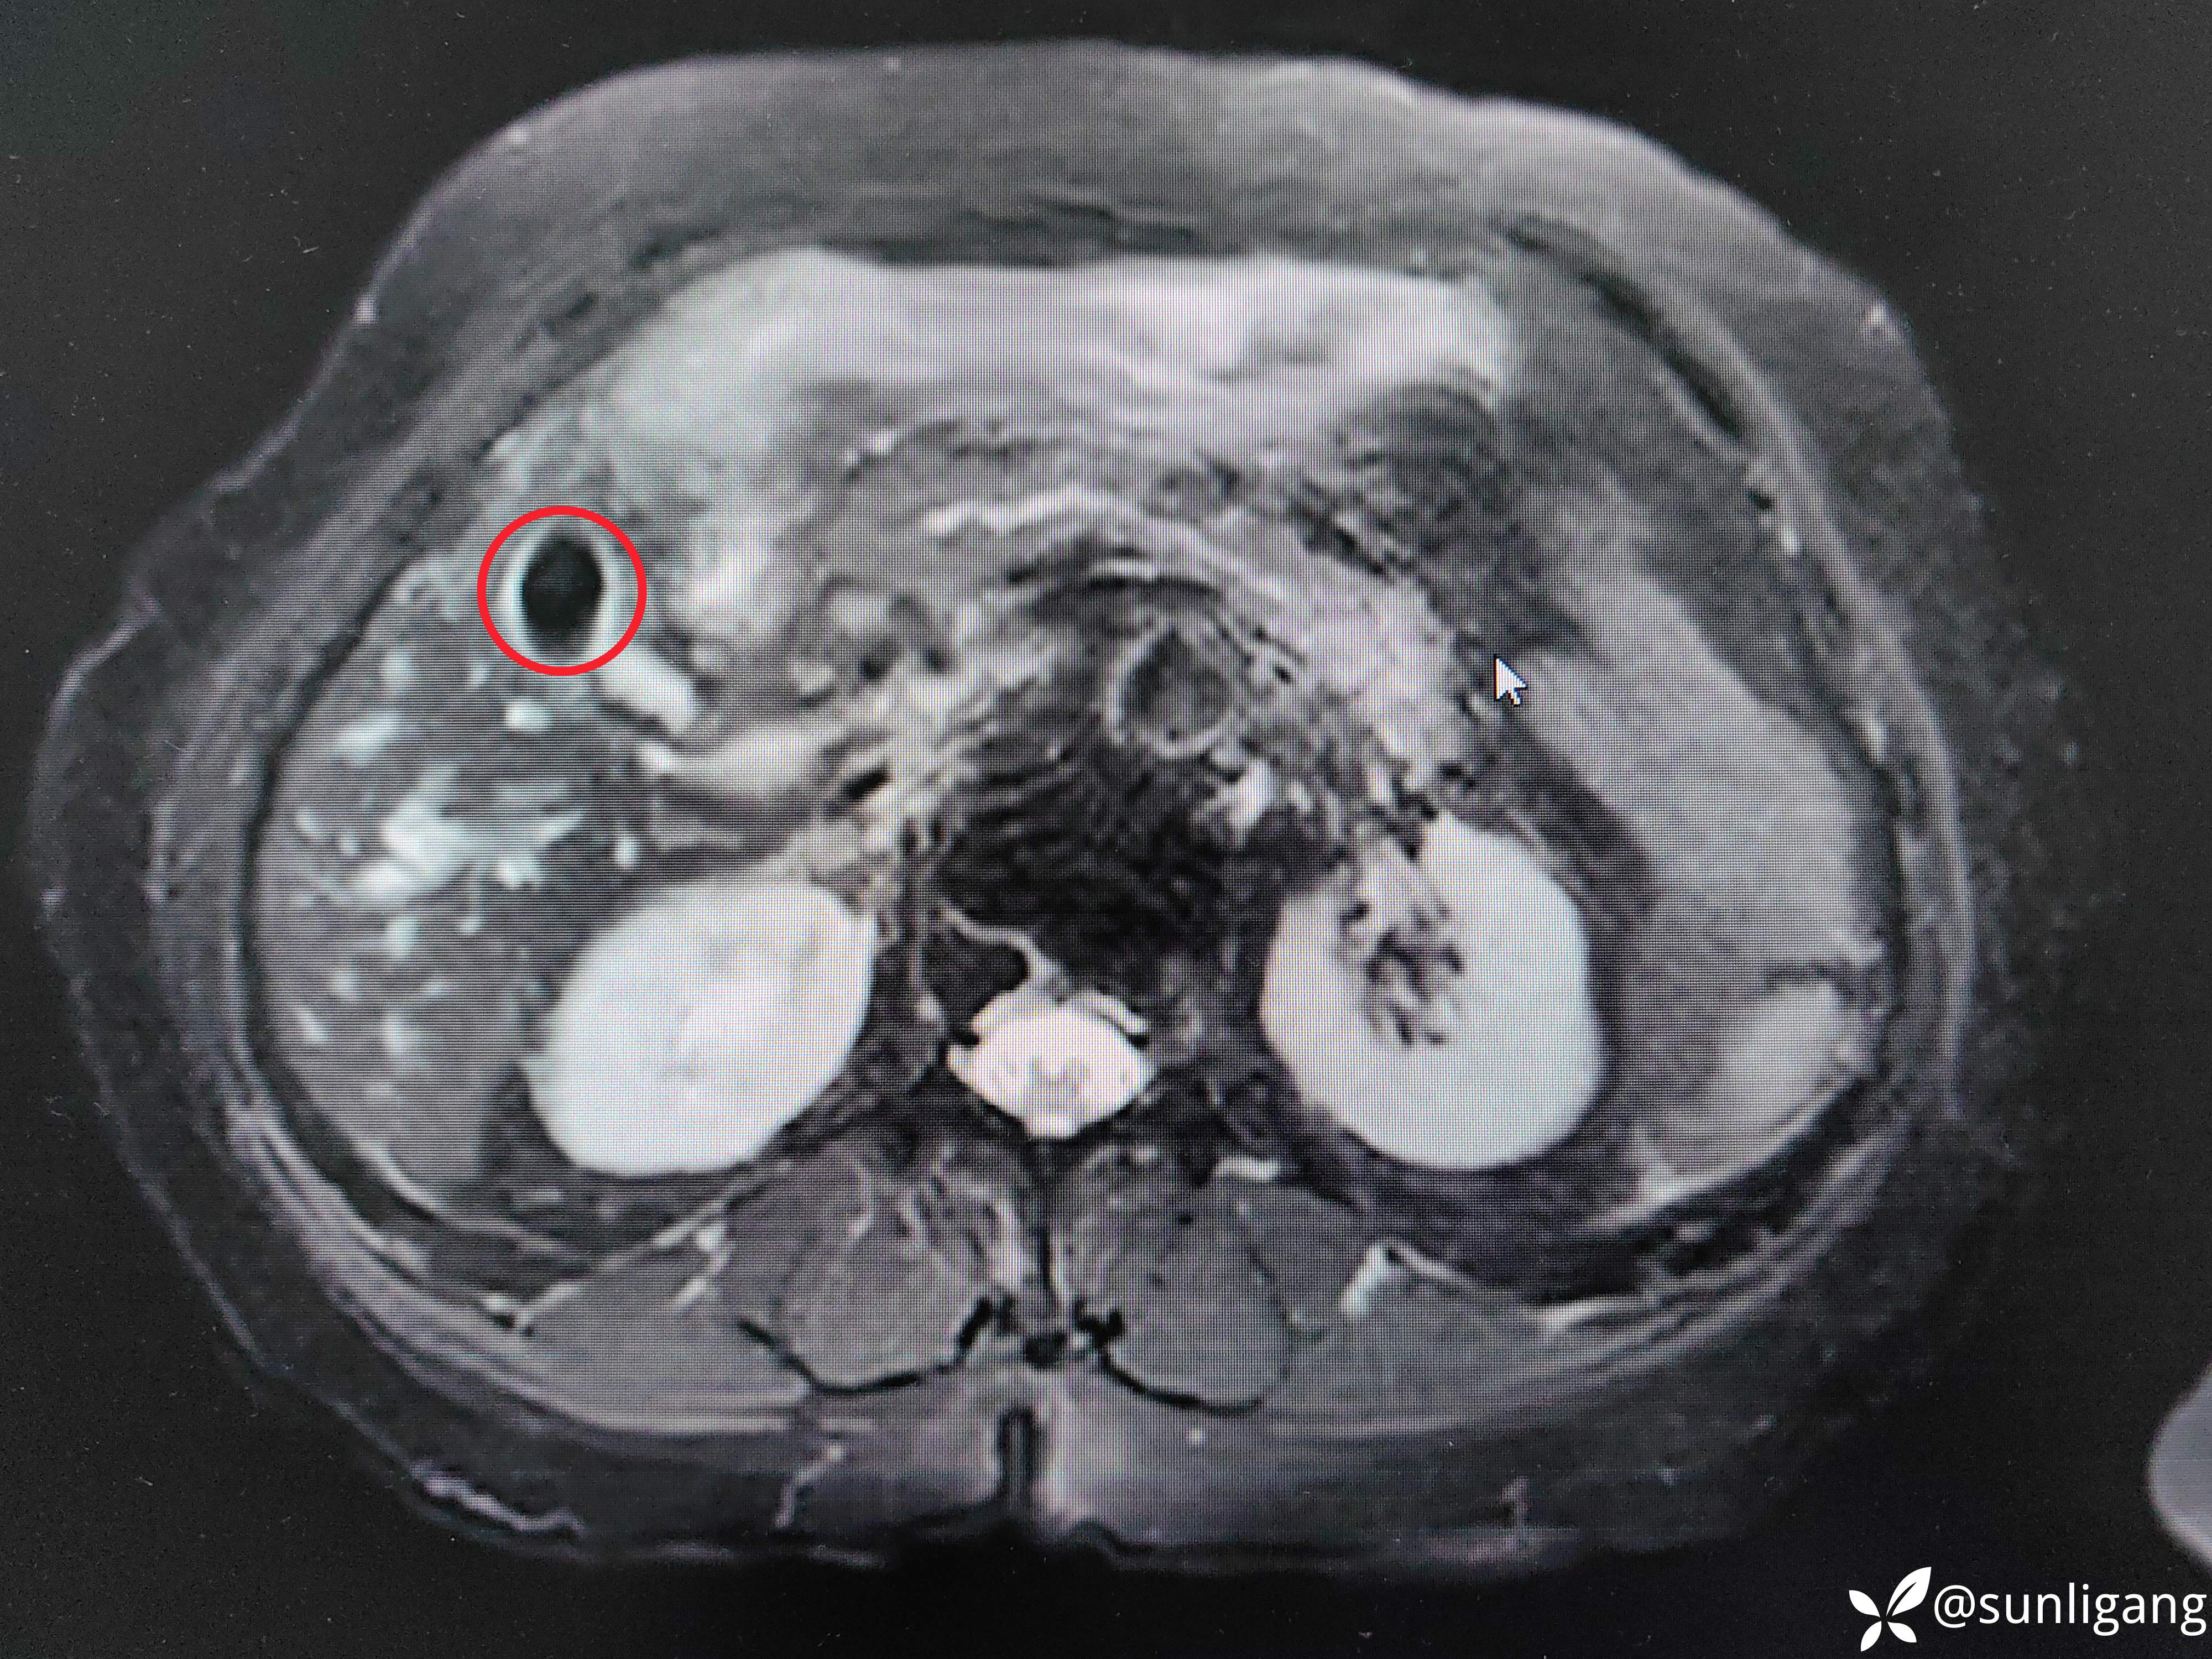

磁共振:

可见明显胆囊结石影

可见中断的中段胆管影以及扩张的肝总管、正常的胰管

可见明显变窄的胆总管(肿瘤直接侵犯?压迫?)